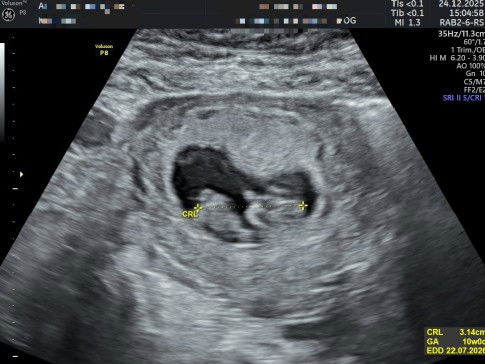

Bund ada yang pernah kah flek terus menerus? Awal mula aku flek tgl 28 Nov ,lsg ke Obgym awal cuma ksih penguat kandungan nobor, trus blm brti akhirnya tgl 2 Des aku ke Obgym lgi dikasih pemberhenti darah n penguat microgest n pling penting disruh bedrest total, masih berlanjut nih smpe skrg flek.a trakhir ke Obgym tgl 24 Des lalu cuma ttep diksih pemberhnti darah n penguat cuma penguat.a ditmbhin dosis.a ,pdahal aku udh bner2 bedrest total Tpi knpa ya klo flek ga berenti2, 😭😭 wlpun debay tetep berkembang tapi ttep aja takut#mohonbantujawabbunda #Sharingdong_Bund #bantujawabanbunda

Bund ada yang pernah kah flek terus menerus? Awal mula aku flek tgl 28 Nov ,lsg ke Obgym awal cuma ksih penguat kandungan nobor, trus blm brti akhirnya tgl 2 Des aku ke Obgym lgi dikasih pemberhenti darah n penguat microgest n pling penting disruh bedrest total, masih berlanjut nih smpe skrg flek.a trakhir ke Obgym tgl 24 Des lalu cuma ttep diksih pemberhnti darah n penguat cuma penguat.a ditmbhin dosis.a ,pdahal aku udh bner2 bedrest total Tpi knpa ya klo flek ga berenti2, 😭😭 wlpun debay tetep berkembang tapi ttep aja takut#mohonbantujawabbunda #Sharingdong_Bund #bantujawab